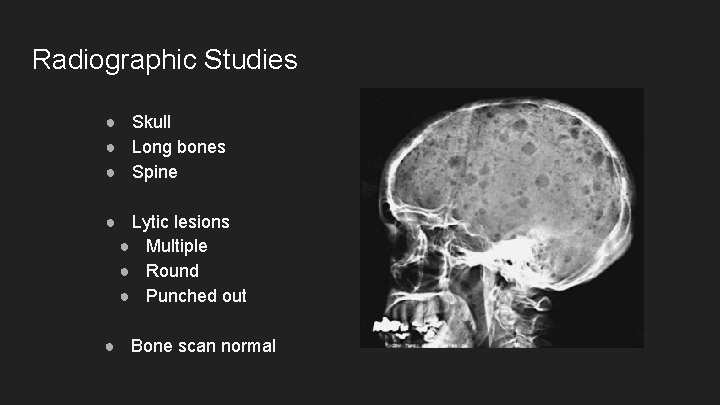

Radiographic Studies ● Skull ● Long bones ● Spine ● Lytic lesions ● Multiple ● Round ● Punched out ● Bone scan normal